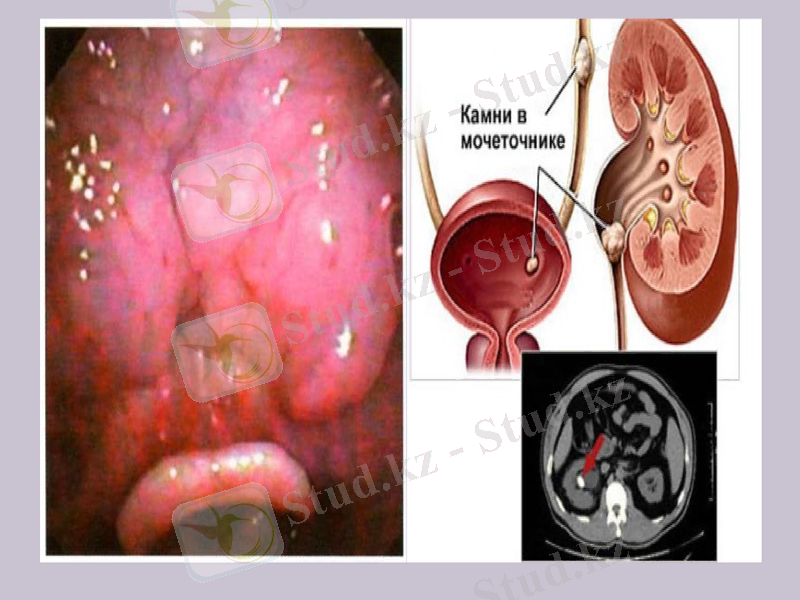

(Латын. Infarcire-толтыру), әдетте жаңа туған төлде кездесетін, оның бүйрегін зақымдайтын дерт. Несеп түтікшелері ішіне, эпителийіне, мүше стромасына несеп қышқылының тұздары шөгеді. Тіліп қарағанда бүйректің үстіңгі қабатында тарам тарам болып орналасқан ақшыл сары, қызғылт сары тұз түйіршіктерін, жолақтарын көруге болады.

Бүйректің несеп қышқылдық инфарктісі

Бұл дерт жаңа туған төл денесінде зат алмасуының күшеюіне байланысты туатын, жаңа тіршілік жағдайына бейімделу реакциясы. Төлдің демалуына, қоректенуіне және оның денесінде зат алмасуының қайта құрылуына байланысты қандағы ядролы эритроциттер жаппай ыдырайды, мұның салдарынан қанда несеп қышқылының мөлшері көбейіп кетеді. төл денесіндегі су мөлшерінің азаюы да процестің өрбуіне қолайлы жағдай.